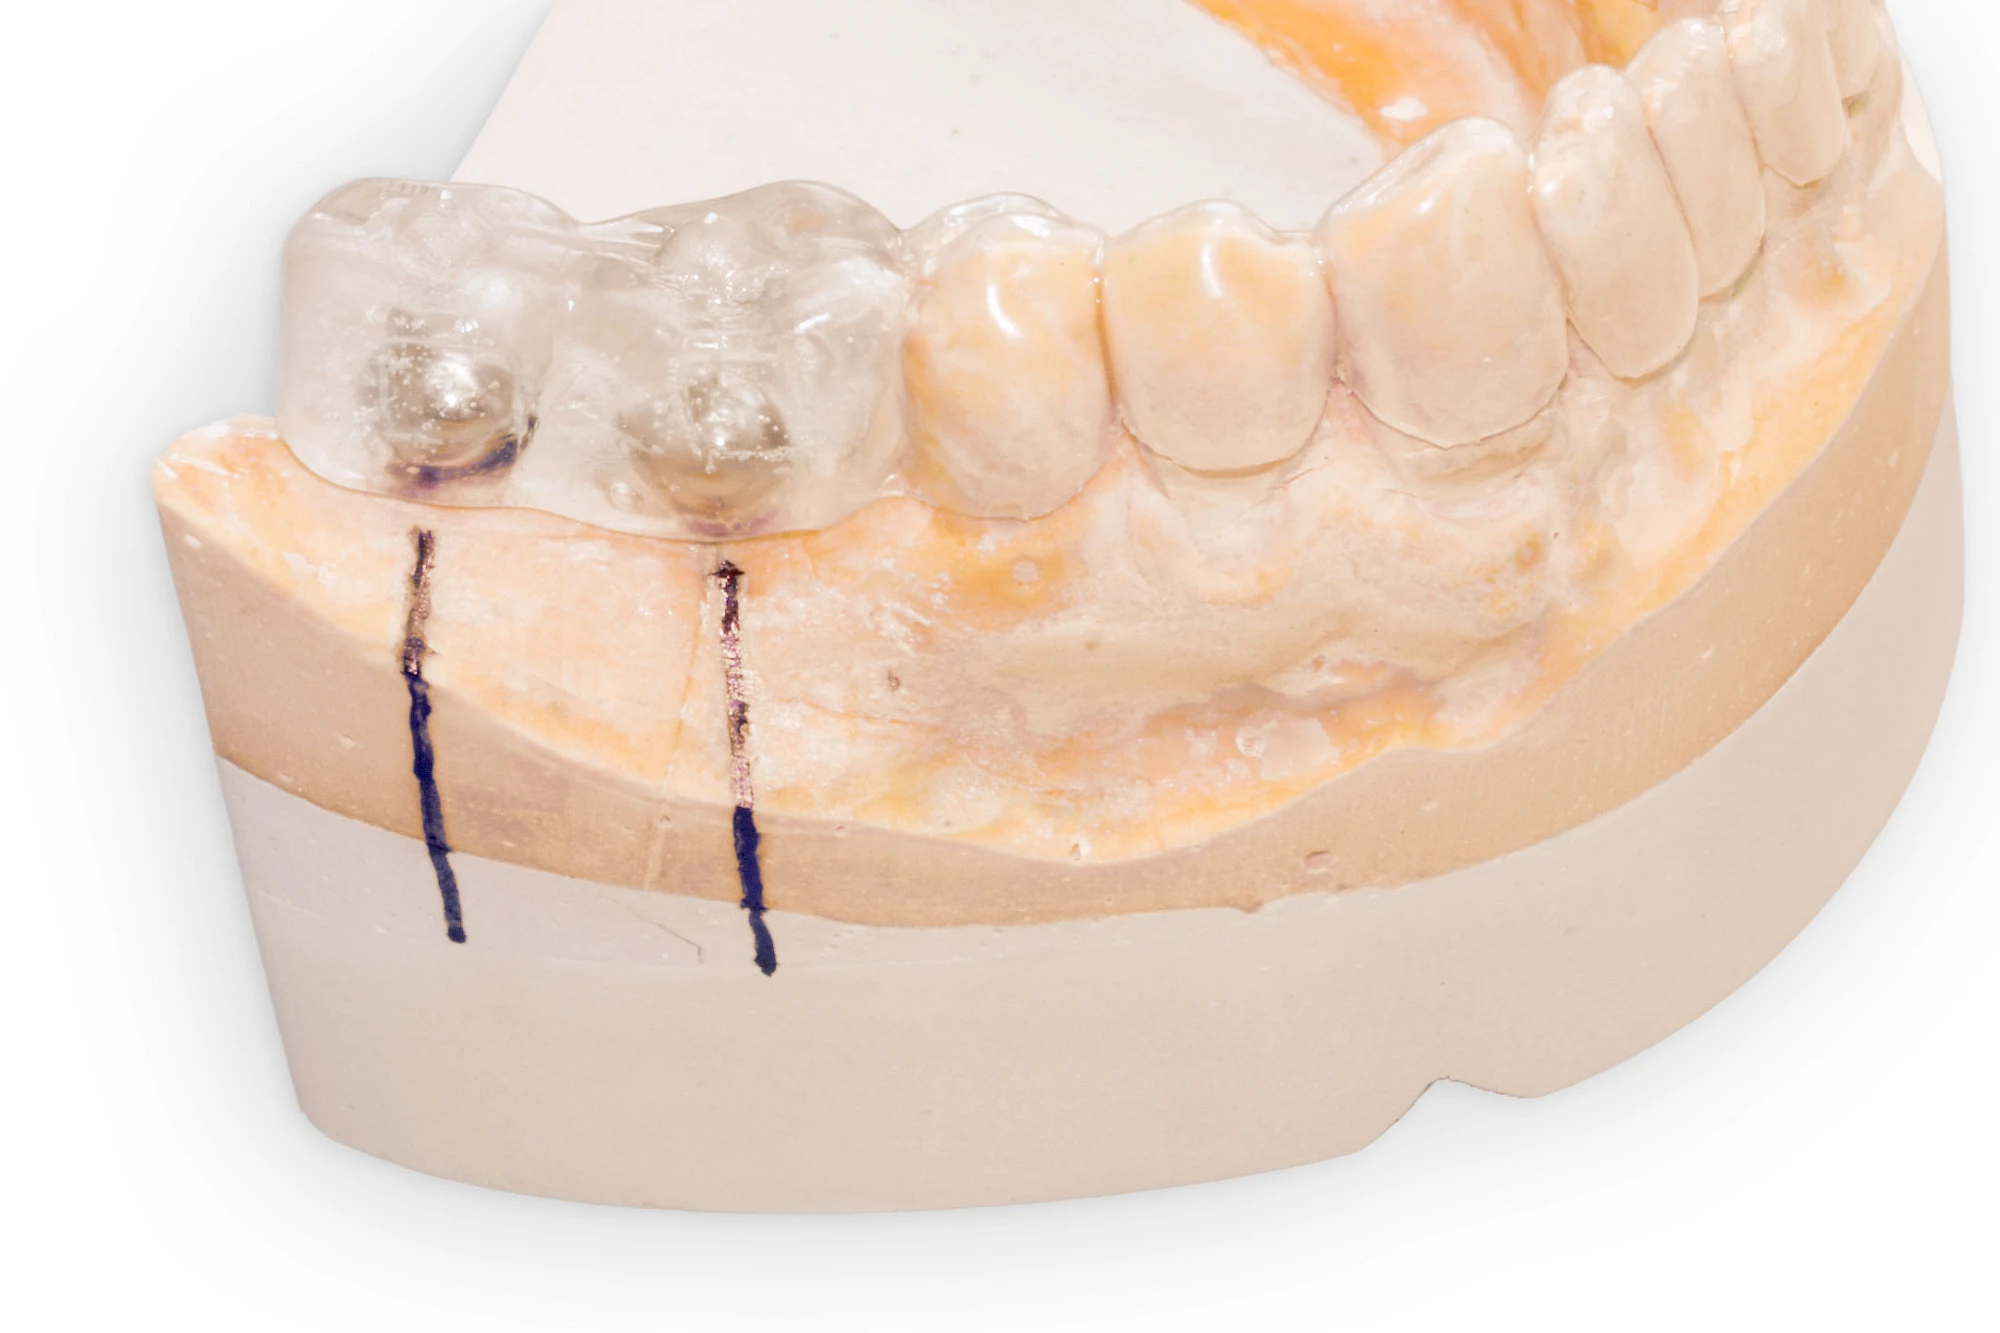

Implantate: Prothesen

Bei herausnehmbaren Prothesen werden Implantate eingesetzt, um den Halt und den Tragekomfort der Prothesen zu verbessern. Dazu kommen verschiedene Verbindungselemente zum Einsatz:

- Teleskope

- Kugelköpfe

- Tellerförmige Lokatoren

- Stege

- Magnete (selten)

Neben rein implantat-getragenen zahnärztlichen Versorgungen werden bei herausnehmbaren Prothesen Implantate auch in Sinne einer "strategischen Pfeilervermehrung" ergänzend zu eigenen Zähnen zur Verankerung eines Zahnersatzes genutzt.

Varianten zur Verankerung von abnehmbarem Zahnersatz auf Implantaten